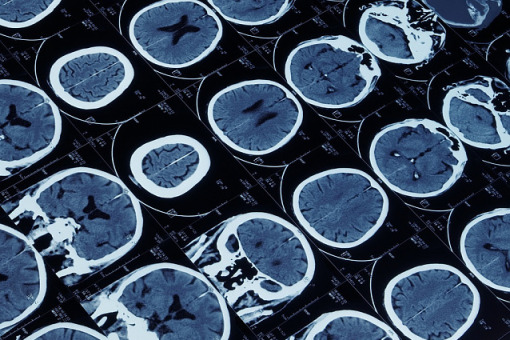

Pierwotne guzy mózgu należą do najbardziej śmiertelnych, a glejak jest najczęstszym nowotworem mózgu. Większość tego rodzaju złośliwych guzów wywodzi się z komórek glejowych, odżywiających i podtrzymujących neurony. Przypada na nie aż 80-90 proc. złośliwych guzów wewnątrzczaszkowych.

Najważniejsza w rozwoju glejaków jest mutacja IDH (enzymu dehydrogenazy izocytrynianowej), pełniącą kluczową rolę w diagnostyce, jak i prognostyce tego nowotworu. Mutacja IDH1/2 jest tzw. mutacją kierująca, zachodzącą we wczesnym etapie onkogenezy i sprzyjająca powstawaniu kolejnych mutacji, napędzających zezłośliwienie komórek nowotworowych.